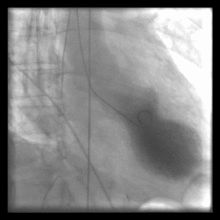

Cardiac Ventriculography is a medical imaging test used to determine a patient's cardiac function in the right, or more typically, left ventricle. Cardiac ventriculography involves injecting contrast media into the heart's ventricle(s) to measure the volume of blood pumped. Cardiac ventriculography can be performed with a radionuclide in radionuclide ventriculography or with an iodine-based contrast in cardiac chamber catheterization.

Radionuclide ventriculography is a form of nuclear imaging, where a gamma camera is used to create an image following injection of radioactive material, usually Technetium-99m (99mTc).